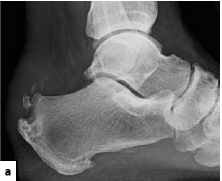

In a recent study published in the Journal of Foot and Ankle Surgery (JFAS), researchers found that 72.9 percent of patients with end-stage ankle arthritis have concomitant hallux rigidus.